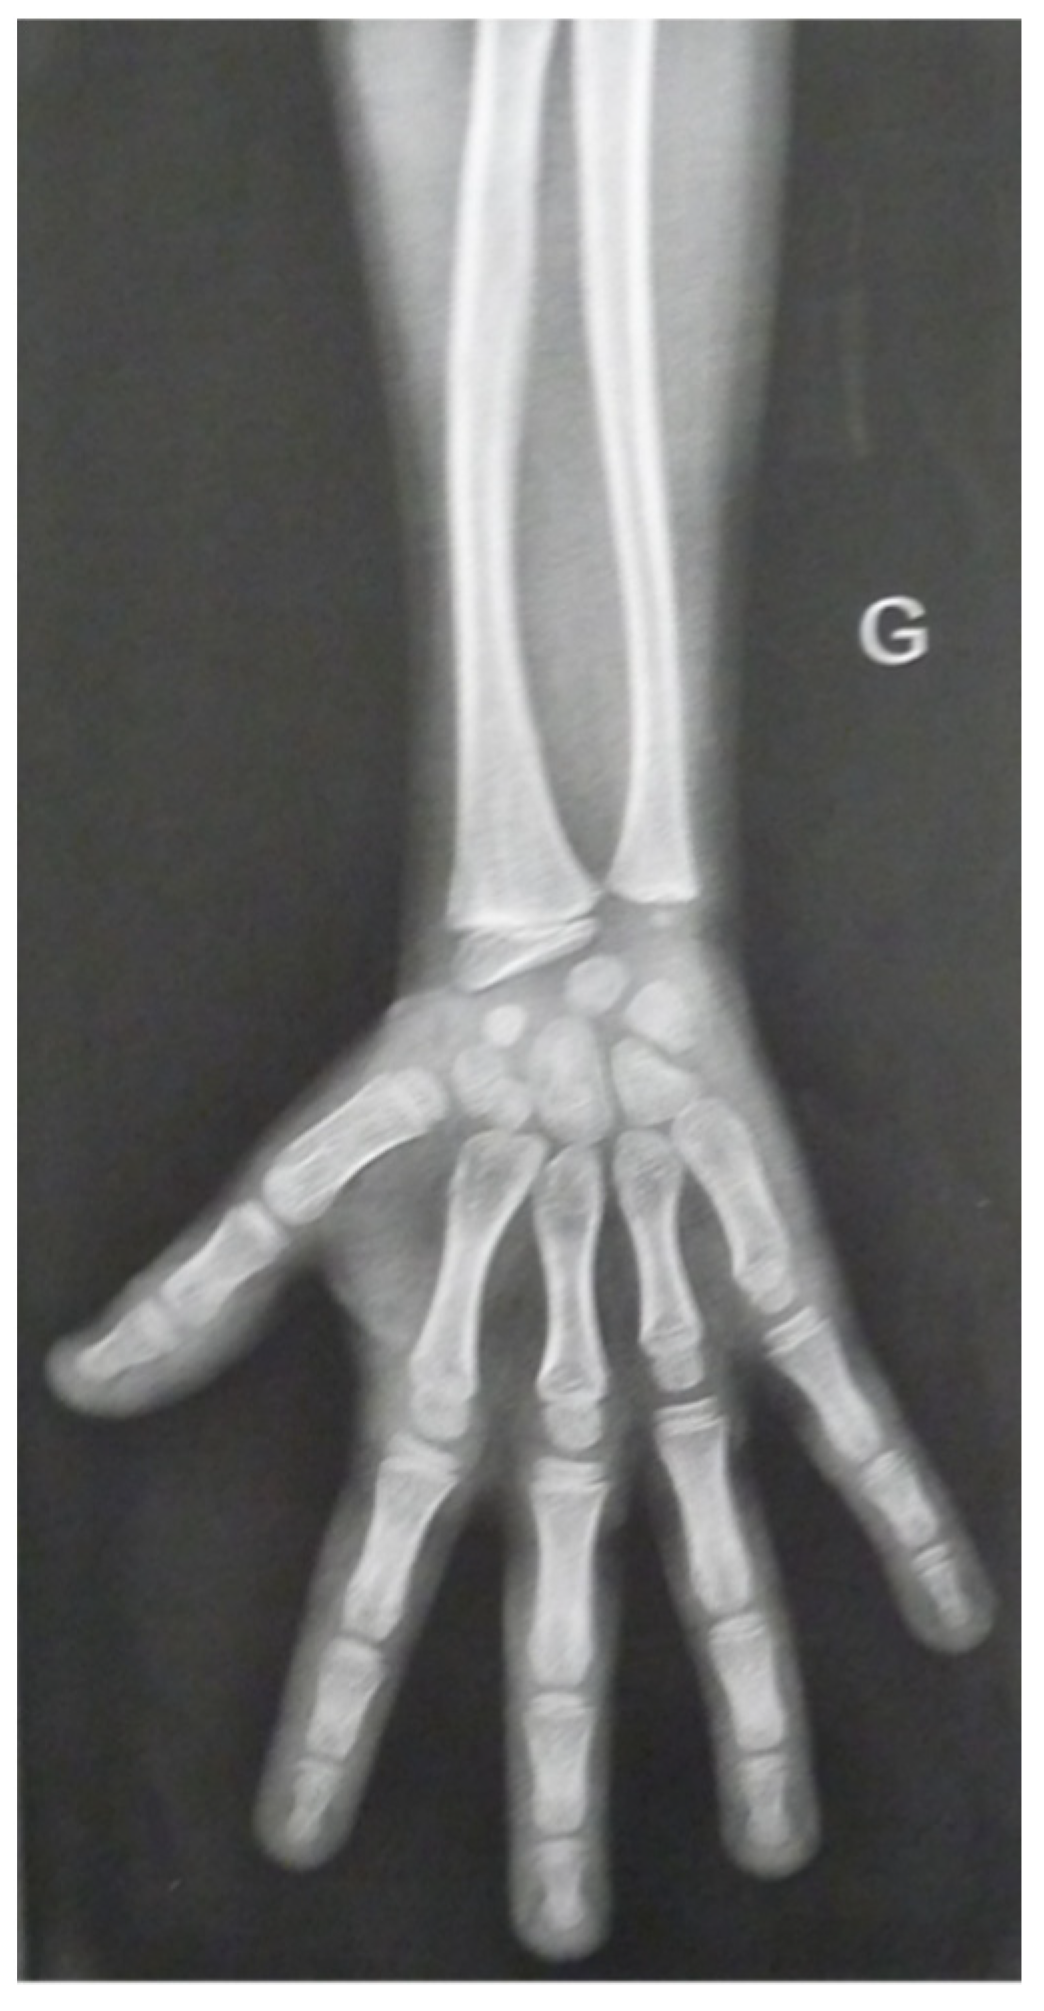

| III.2 | Short stature, mesomelia, scoliosis, genu varum, brachymesophalangia, dyschondrosteosis, Madelung deformity, psoriasis, hyperthyroidism, late puberty | −4.0 SD | c.452G>A; p.Ser151Asn c.6833-1G>A; p.? | SHOX, ACAN | Heterozygous for both |

| Main skeletal features | Mesomelic shortening, brachymesophalangia, dyschondrosteosis | Mesomelic shortening, scoliosis; genu varum, brachymesophalangia, dyschondrosteosis, Madelung deformity | Mild rhizo-mesomelic shortening, joint anomalies, early-onset osteoarthritis | Acrodysostosis, cone-shaped epiphyses, acroscyphodysplasia, bone age advancement |